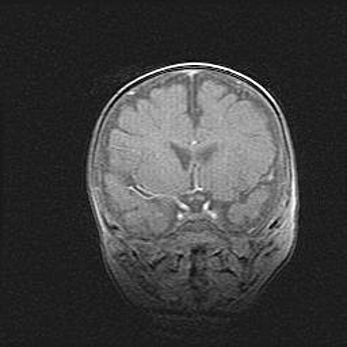

Церебральная ишемия II.

Возраст: 7 дней

Вес: 3350 г

Пол: женский

Окружность головы: 35 см

Срок гестации: 39 недель

Ишемия головного мозга – это состояние, которое развивается в ответ на кислородное голодание вследствие недостаточного мозгового кровообращения. У новорожденных она является следствием дефицита кислорода, что ведет к метаболическим расстройствам различной степени тяжести в тканях головного мозга, в том числе к развитию коагуляционных некрозов и гибели нейронов.